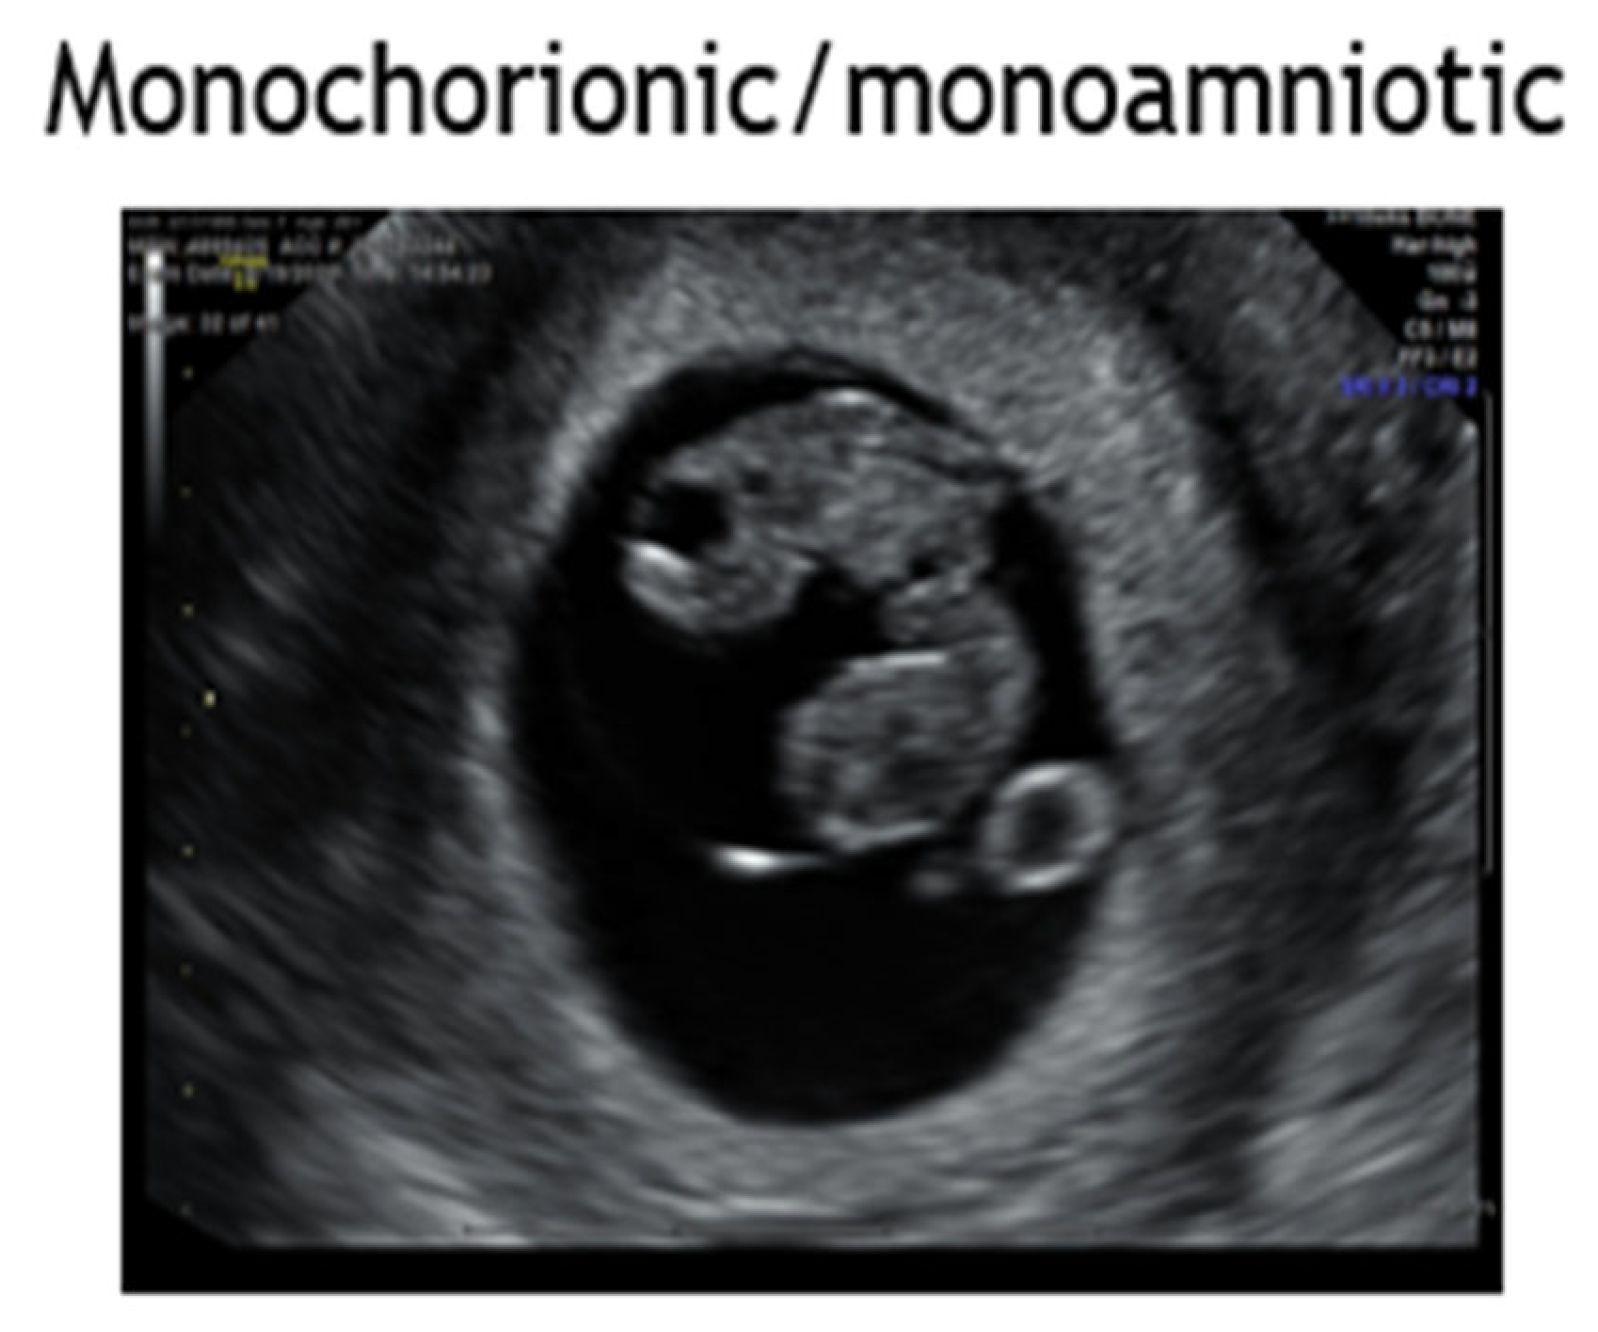

4.6. Monochorionic Monoamniotic Twins

- Evidence supports delivery of monoamniotic twin pairs at 32-34 weeks by cesarean delivery given risk for stillbirth and inter-locking twins in parturition [Level III; B].